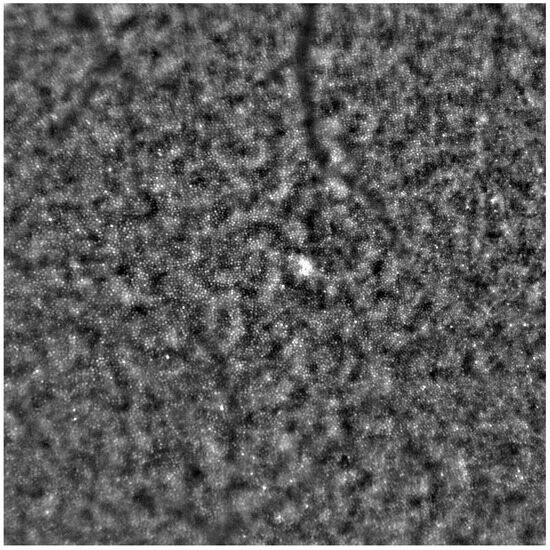

Adaptive optics retinal images depicting a healthy eye, CD, CRD, and STGD are presented in Figure 1, Figure 2, Figure 3 and Figure 4.

Cone mosaic disruption is an abnormality typical of IRDs. The cone and rod spacing is increased in IRDs compared to healthy retinas [18]. Additionally, poor image quality, likely resulting from inadequate fixation in eyes with low visual acuity, is a problem that, in some cases, makes image acquisition impossible [19,20]. In STGD, as well as in other IRDs, the “dark spaces” depicting areas of disrupted cone structure and abnormal cone reflectance have been described [21,22].

Figure 4. An adaptive optics image of the photoreceptors of the eye with Stargardt disease (Rtx1™; Imagine Eyes, France). The photoreceptor mosaic is disrupted, note the appearance “dark spaces” among the cone mosaic in various regions of the picture.